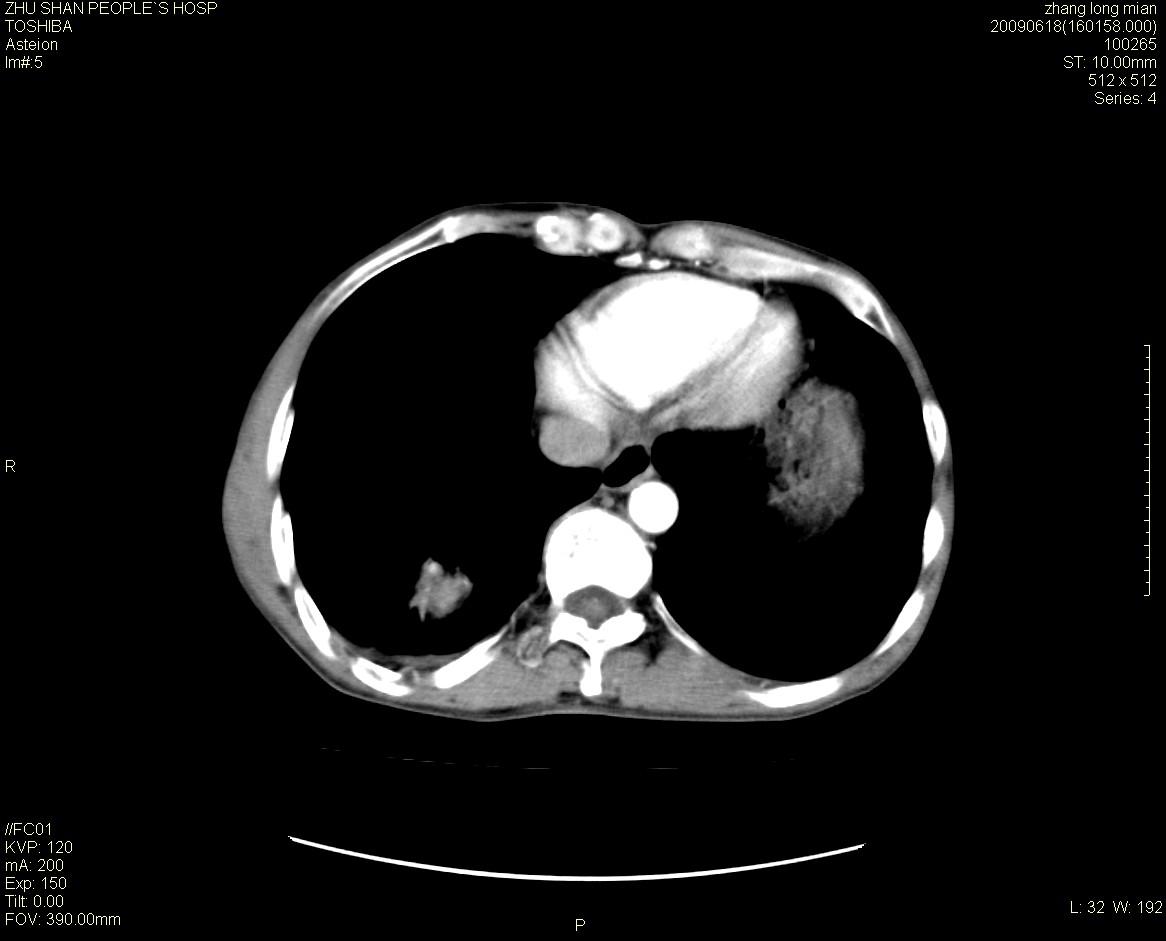

男性 65岁 胸片发现右下肺包块.诊断肺ca并纵隔转移没有问题吧!

肺ca并纵隔转移,阻塞性炎症。

两侧胸廓不对称,右侧呈塌陷改变,右肺萎缩。

右下肺见浅分叶状软组织块影,边缘有毛刺,其下部似见不完整偏心空洞影,邻近胸膜凹陷征,并胸腔积液。

增强见纵隔区气管隆突上下及左肺门区肿大淋巴结。左肺感染性病灶。

另见右上肺见一枚小结节影,性质待定。